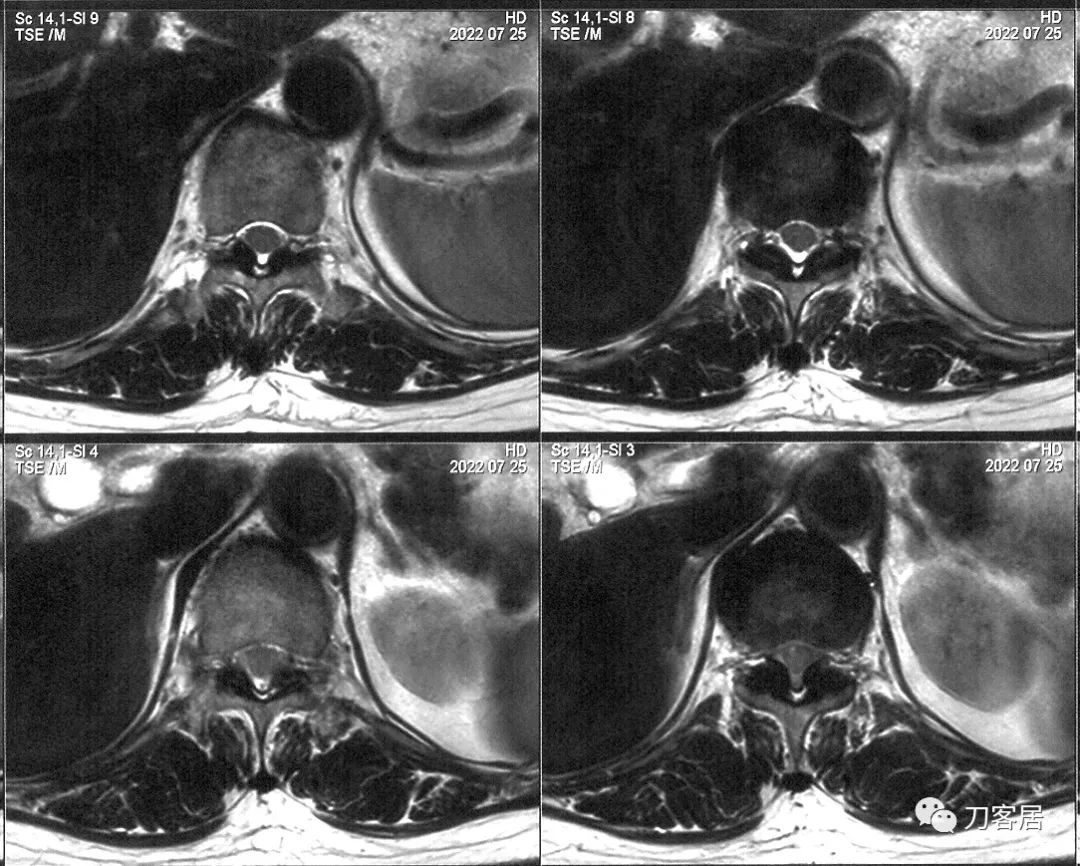

患者于7月25日,在我院做了颈椎MRI, 头颅MRI和胸椎MRI。颈椎MRI提示颈5-6椎间盘突出,颈3椎体信号改变,胸6椎体血管瘤,胸椎MRI提示胸11-腰1黄韧带肥厚,胸椎管狭窄。颅脑MRI未见明显异常。双下肢电生理检查提示双侧腓运动神经波幅降低。

图5. 20220725西京医院术前胸椎MRI1,显示胸6椎体血管瘤,胸11-腰1黄韧带肥厚,椎管狭窄。

图6. 20220725西京医院术前胸椎MRI2,显示胸11-腰1黄韧带肥厚,椎管狭窄。